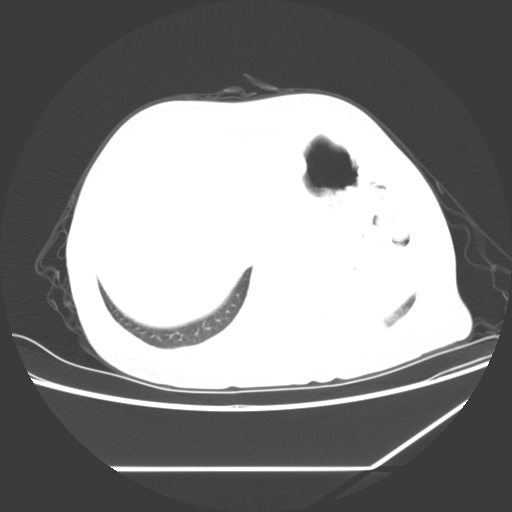

标题: CT25393:病人45岁,咳嗽,吐黄痰带血丝,发热,胸闷月余 [打印本页]

标题: CT25393:病人45岁,咳嗽,吐黄痰带血丝,发热,胸闷月余

1、左肺中央型肺癌并双肺弥漫性转移   2、双肺部感染    3、肺大泡     4、左侧胸腔积液

双侧肺弥漫性病变,可见“空泡征”及“蜂窝征”,考虑肺泡癌可能性大,左侧胸腔积液,考虑胸膜受累可能!

1)不排除肺泡癌可能。2)左侧胸腔积液。